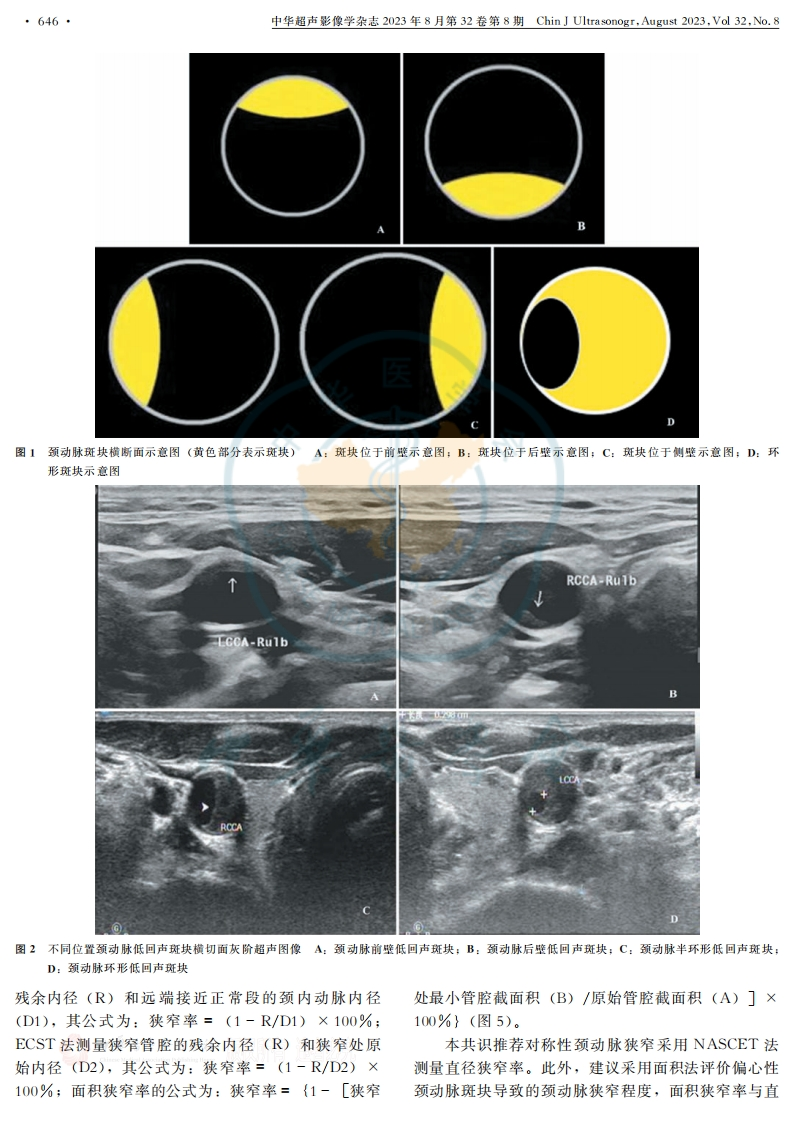

中华超声影像学杂志2023年8月第32卷第8期Chin J U1 trasonogr,August2023,Vdl32,No.8·645··标准与规范·超声评价颈动脉易损斑块中国专家共识(2023版)中国医师协会超声医师分会通信作者:何文,首都医科大学附属北京天坛医院,北京100070,Email:168 hewen@sina.com;勇强,首都医科大学附属北京儿童医院顺义妇儿医院,北京101300,Email:doctor-yong@163.comD01:10.3760/cma.j.cn131148-20230418-00215Chinese expert consensus on ultrasound evaluation of vulnerable carotid plaque(2023 edition)Ultrasound Doctor Branch of Chinese Medical Doctor AssociationCorresponding author:He Wen,Beijing Tiantan Hospital,Capital Medical University,Beijing 100070.China,Email:168hewen@sina.com:Yong Qiang,Shunyi Women's &Children's Hospital of BeijingChildren's Hospital,Capital Medical University,Beijing 101300,China,Email:doctor-yong@163.comD0I:10.3760/cma.j.cn131148-20230418-00215多项研究表明颈动脉稳定型斑块不易产生有症状内侧、外侧、前壁、后壁或描述为环形/半环形斑块,颈动脉栓塞或闭塞,而狭窄程度不严重的颈动脉易损如“左侧颈动脉最大斑块位于颈总动脉中段内侧壁”斑块山更易产生症状性颈动脉栓塞或闭塞等后果。目“颈内动脉起始斑块为环形斑块”等。图1为颈动脉前国内外关于颈动脉斑块的诊治指南或共识多基于临斑块不同位置横切面示意图,图2为颈动脉斑块不同床的诊治指南,对于颈动脉易损斑块的超声检查流01位置的横切面灰阶超声图像。程、内容等尚未达成共识。鉴于颈动脉易损斑块超声Naghavi等[☒将伴有严重钙化、陈旧性血栓且偏检查的重要性,中国医师协会超声医师分会组织全国A心的慢性狭窄性斑块定义为易损斑块,且有研究显示部分血管超声专家通过对国内外重要文献及相关指南颈动脉直径狭窄率<50%的隐源性卒中患者存在偏心阅读及讨论,并结合我国的临床实践情况,提出关于性颈动脉易损斑块),因此在颈动脉斑块超声检查描颈动脉易损斑块的超声诊断专家共识,重点阐述超声述中一定要说明颈动脉斑块的准确位置。评价颈动脉易损斑块的检查流程、方法及临床价值,(二)颈动脉斑块大小的超声描述旨在促进我国颈动脉易损斑块超声检查的规范化。超声评估颈动脉斑块大小时,若存在多发颈动脉易损斑块定义为所有具有破裂倾向、易发生血栓斑块,建议选取最大斑块进行测量。横切面扫查测量形成和(或)进展迅速的危险斑块),研究表明斑块斑块最大厚度值,纵切面扫查测量斑块长度值,建议易损性相关因素主要包括:①斑块内出血;②占斑块以长度值(mm)×最大厚度值(mm)表示斑块大体积40%以上富含脂质成分的坏死核心;③薄纤维小(图3,4)。帽(纤维帽厚度<1004m);④斑块内活动性炎症;颈动脉斑块最大厚度定义为颈动脉所有斑块中最⑤斑块内新生血管;⑥斑块体积:⑦斑块厚度;⑧斑大横向厚度。研究表明颈动脉斑块最大厚度和斑块体块表面形态「)。超声评价颈动脉易损斑块应包括斑块积是斑块易损性相关危险因素,其中最大厚度意义更大小、位置、范围、形态、回声特征及表面有无遗大)。较大斑块导致颈动脉狭窄,从而引起狭窄远端疡、血栓等,检测血流动力学参数及评估血管狭窄程脑血流呈低灌注状态,造成相应供血部位的脑组织发度,必要时应用超声造影、三维超声等超声新技术,生缺血缺氧、坏死。对颈动脉斑块进行更全面的评估。大部分评估颈动脉直径狭窄率的研究采用的是欧一、颈动脉常规超声扫查要求洲颈动脉外科试验法(European Carotid Surgery(一)颈动脉斑块扫查切面及位置描述Trial,ECST)和北美症状性颈动脉内膜切除试验法本共识推荐颈动脉斑块扫查采用纵切面与横切面(North American Symptomatic Carotid Endarterectomy相结合,描述斑块位于颈总动脉、颈内、颈外动脉的Trail,NASCET)[a。NASCET法测量狭窄管腔的